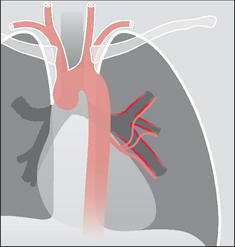

image

Figure 30.5 Haemoptysis due to pulmonary thromboembolic disease. Emboli have lodged in the low pressure pulmonary arterial circulation. An embolus may cause a mild or moderate haemoptysis.